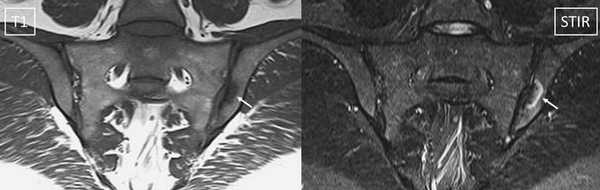

МР-скан коксофеморальных сочленений, вариант нормы

Интерпретацией изображений занимается врач-рентгенолог. В норме на серии томограмм травматических изменений не определяется:

структура костной ткани однородна, без дистрофических признаков;

субхондрального склероза суставных поверхностей нет;

капсула сочленений не утолщена, в полости присутствует небольшое количество синовиальной жидкости с однородным МР-сигналом;

костные крыши вертлужных впадин сформированы правильно, суставные щели равномерные, конгруэнтность (сопоставимость, согласованность) поверхностей сохранена;

целостность связочного аппарата не нарушена;

сигнал хрящевого компонента без особенностей, областей истончения нет;

краевые заострения суставных поверхностей вертлужных впадин отсутствуют;

окружающие мягкие ткани без видимой патологии;

бедренные и тазовые кости в зоне сканирования без очаговых изменений.